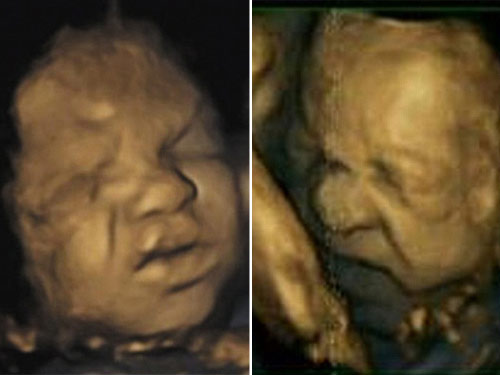

Các nhà khoa học phát hiện ở những tuần chuẩn bị chào đời, các bào thai có những biểu hiện như người lớn: Cau mày, nhăn nhó trong bụng mẹ.

Một nhóm nghiên cứu từ Đại học Durham (Anh) đã thực hiện siêu âm 4D bốn lần với 15 phụ nữ trong suốt quá trình mang thai. Sau đó, các nhà nghiên cứu đã phân tích hình ảnh thu được từ video và phát hiện các biểu cảm của như nhăn mũi, nhíu lông mày cũng như các sắc thái khác trên khuôn mặt người lớn lúc đau khổ đều tồn tại ở thai nhi.

Trong lần quét đầu tiên lúc 24 tuần tuổi, các nhà nghiên cứu hiếm khi tìm thấy sự kết hợp của các biểu cảm này. Tuy nhiên, theo báo cáo trên tạp chí PLoS ONE, đến tuần thứ 36 trở lên hay một tháng cuối trước khi chào đời, cả bé trai và gái đều liên tục có những biểu cảm như đay đớn, khó chịu.

Hình ảnh thai nhi cau có

Trong khi đó, Tiến sĩ Reissland- người đứng đầu nhóm nghiên cứu – không tin rằng những biểu hiện nhíu mặt, cau mày là biểu hiện sự đau đớn của trẻ. Bởi khi thực hiện siêu âm, thai nhi trong trạng thái hoàn toàn khỏe mạnh, người mẹ cũng đang thư giãn, nghỉ ngơi. Theo ông, đó chỉ là sự biểu hiện của sự trưởng thành não bộ và hệ cơ, đồng thời là “bài tập” giúp các bé sẵn sàng bước vào đời.